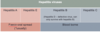

What are types of gram posive cocci?

What are types of gram negative cocci?

What are types of gram positive bacilli (aerobes and anaerobes)?

What are types of gram negative bacilli?

What are types of gram negative coccobacilli?

What are types of spiral bacteria?